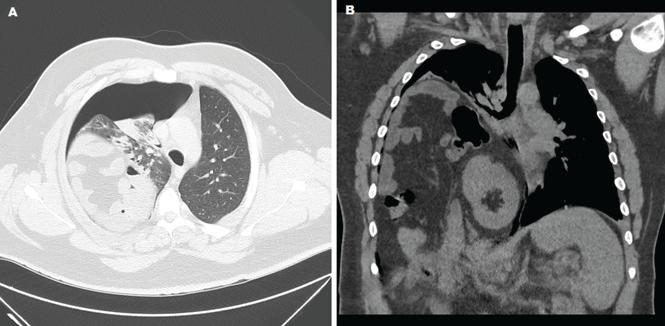

Radiography shows a large right pneumothorax and an elevated right diaphragm (Figure 1). Computed tomography (CT) (Figure 2) reveals a right anterior apical pneumothorax with hypoplastic lung and significant elevation of the right diaphragm with fat, bowel, and kidney within the right thorax. He is hemodynamically stable and shows no signs of bowel obstruction.

Thoracic computed tomography shows right anterior apical pneumothorax with atelectatic and hypoplastic lung in a cross-sectional view (A). A coronal view (B) shows significant elevation of the right hemidiaphragm, with fat, bowel, and kidney within the right hemithorax.